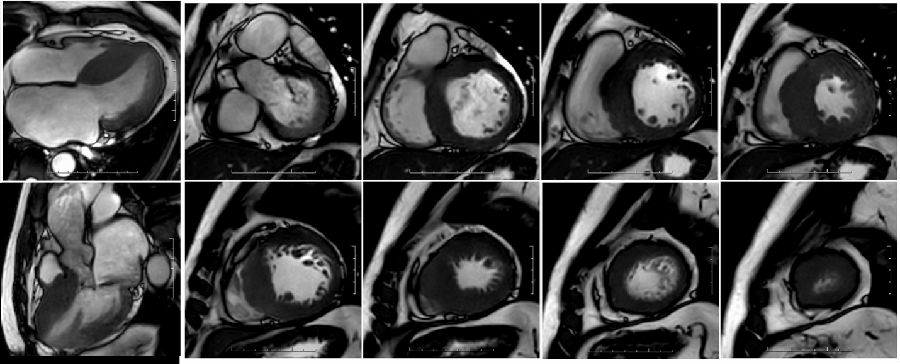

此外,近年来兴起的CMR Tx mapping参数定量技术,包括T1 mapping和细胞外间质容积分数(ECV)、T2 mappingT2* mapping进一步丰富了磁共振心肌组织特征评估的手段与方法(图3这些技术能够更早期定量评估心肌组织学异常,对心血管疾病的早期诊断和早期治疗具有巨大潜力。

3. Tx mapping技术能够在体定量评估心肌水肿、坏死、纤维化、出血等多种病理组织学改变